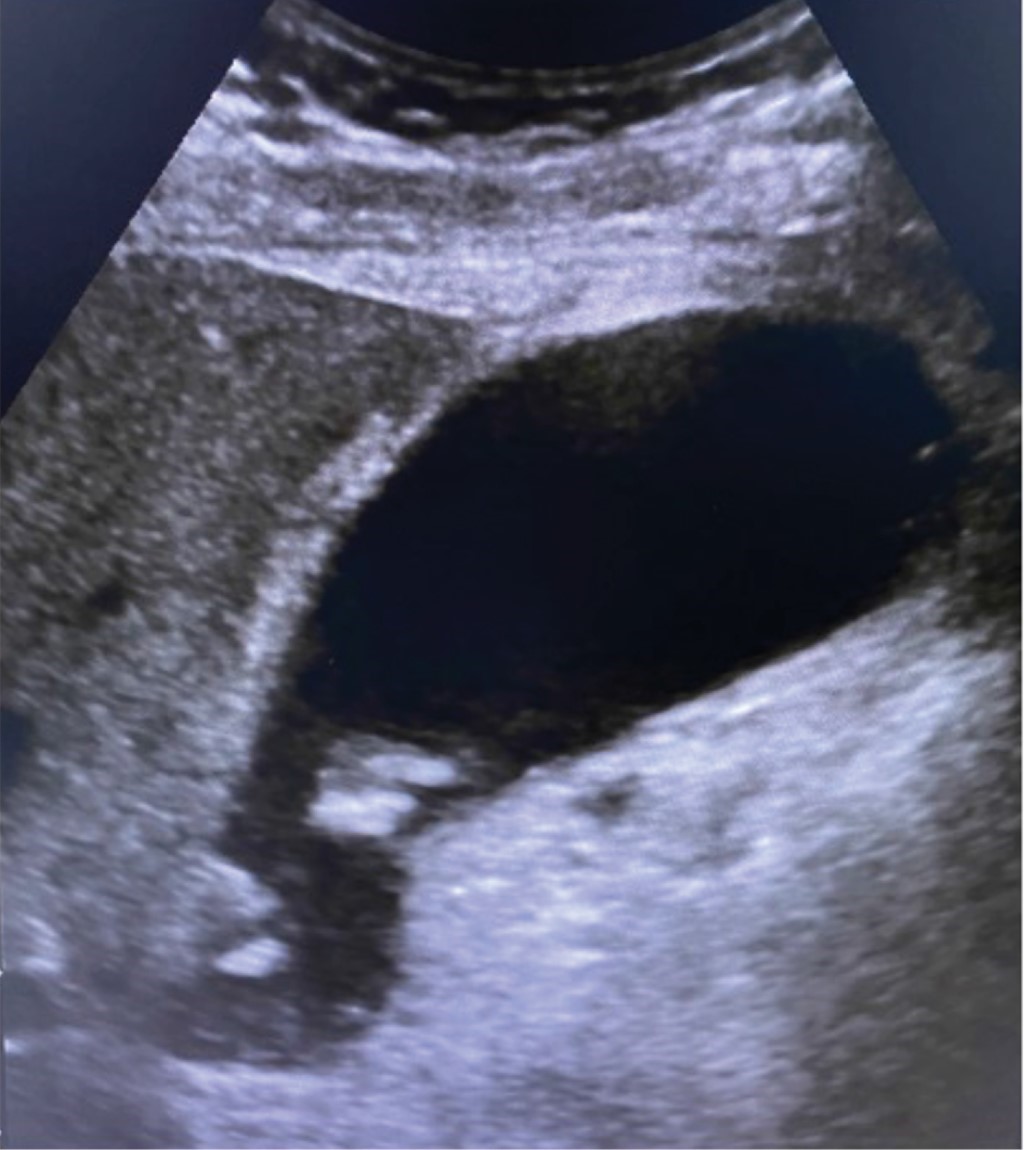

La primera imagen que presentamos muestra el ultrasonido de un paciente masculino de 70 años que acudió a urgencias por dolor epigástrico, náusea y vómito. A la exploración física no presentaba datos de irritación peritoneal o signo de Murphy, probablemente debido a que había recibido analgésicos opioides previamente. Tampoco se encontraron alteraciones en sus laboratorios de ingreso. La interpretación del ultrasonido inicial describió sólo la presencia de lodo biliar pero "sin datos de inflamación" al momento del estudio, ausencia de cálculos en su interior, distensión vesicular "satisfactoria", pared con grosor de 1.6 mm y colédoco con calibre de 3.2 mm (Figura 1).

Figura 1